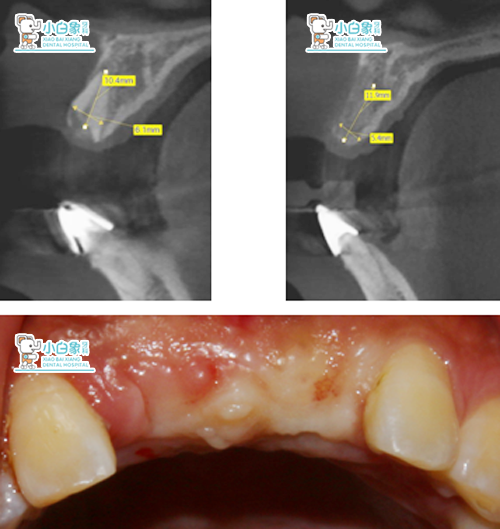

检查:合面部未见异常,口内查:11、21牙槽嵴丰满度尚可,牙龈颜色正常,扪诊未见明显骨质隆突。

X线示:11见断根影像。

X线片+口内像